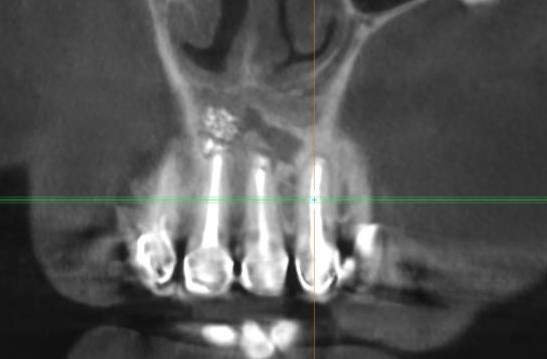

Спустя три года виден следующий результат :

Практически полное закрытие дефекта в области операции

На ЗД реконструкции заметно отсутствие костного дефекта